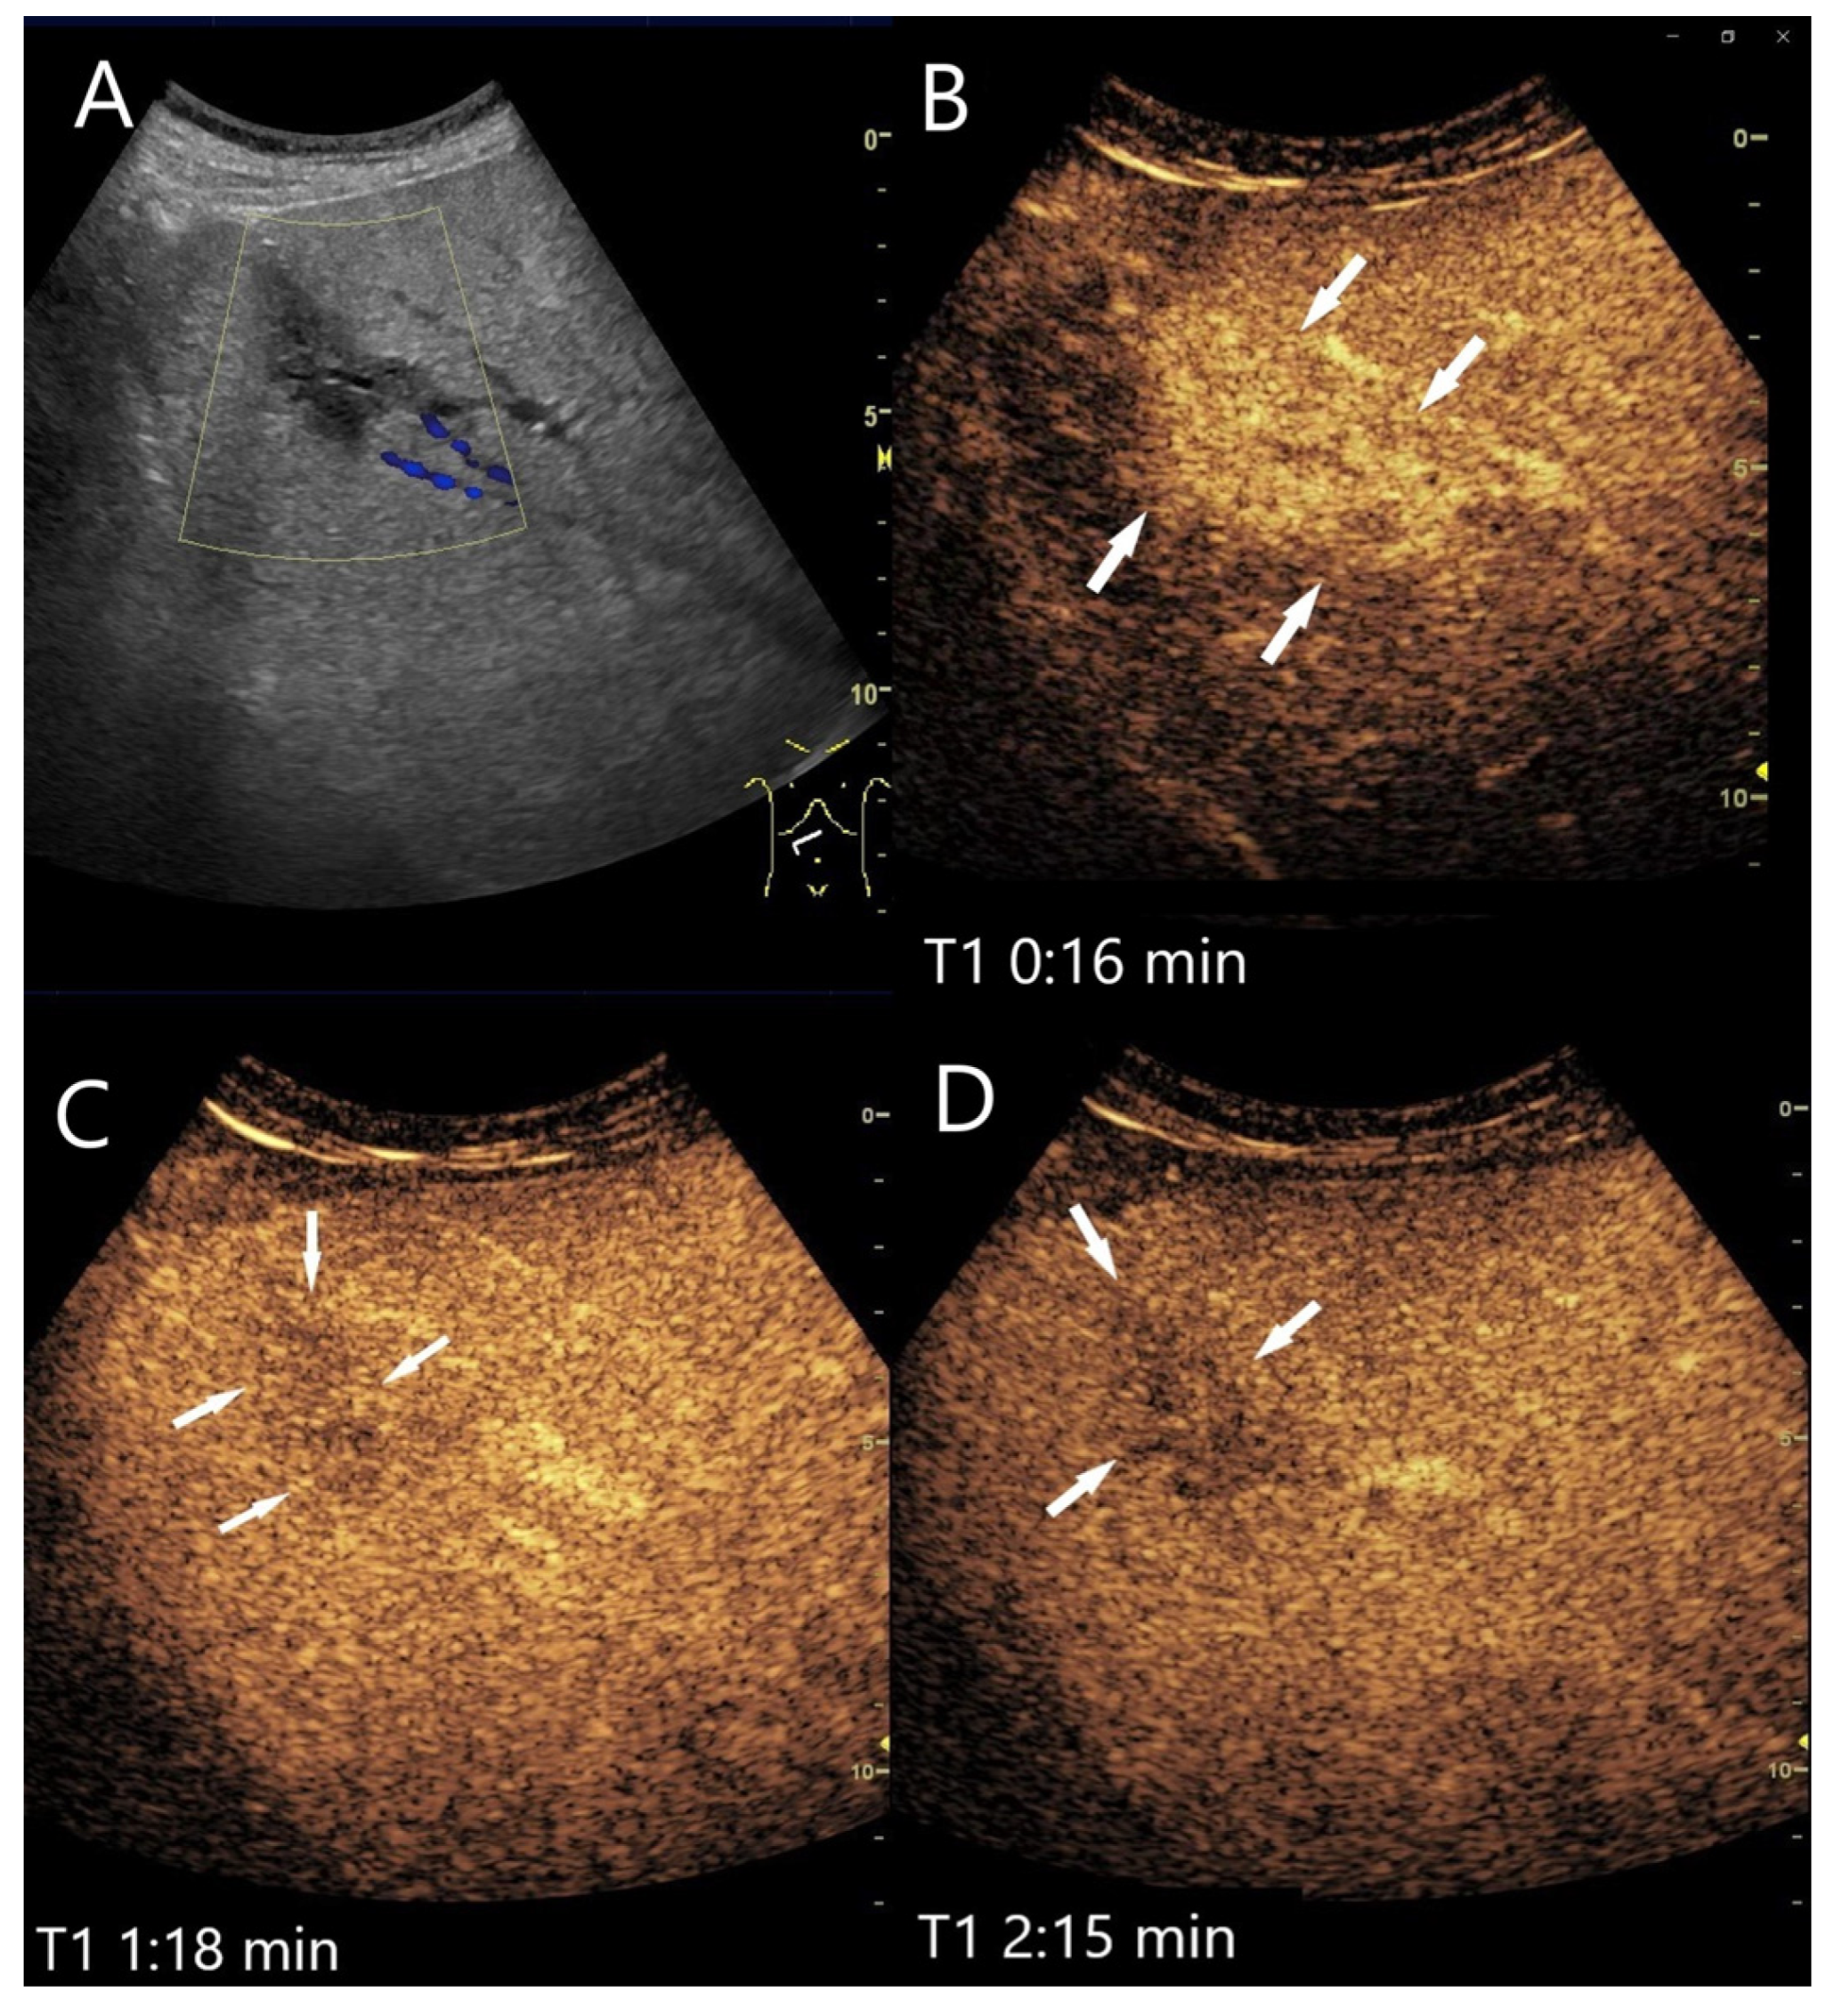

| Hemangioma | Hyperechoic, beyond liver veins, hypoechoic in steatosis and with shunts. | Peripheral globular enhancement, centripetal filling. Rapid homogeneous filling in shunt hemangiomas. | Hyperenhancement and isoenhancement. | Permanent video loops with destruction of the UCA bubbles and slow refill. Fibrosis. |